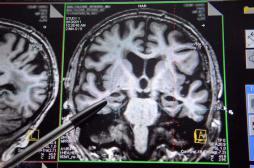

Creutzfeldt-Jakob